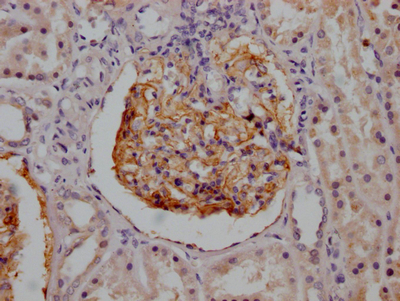

• IHC image of CSB-RA714310A0HU diluted at 1:100 and staining in paraffin-embedded human kidney tissue performed on a Leica BondTM system. After dewaxing and hydration, antigen retrieval was mediated by high pressure in a citrate buffer (pH 6.0). Section was blocked with 10% normal goat serum 30min at RT. Then primary antibody (1% BSA) was incubated at 4℃ overnight. The primary is detected by a Goat anti-rabbit IgG polymer labeled by HRP and visualized using 0.05% DAB.